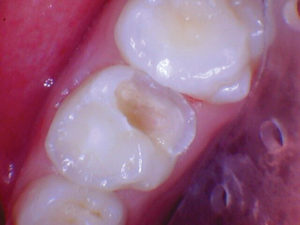

Caso 5

Una adolescente de 13 años presentada para un nuevo examen de paciente. Se observó una gran lesión cariosa en el primer molar permanente superior izquierdo, que presentaba síntomas de pulpitis reversible. Las opciones de tratamiento se discutieron con la paciente y su madre. Mis objetivos personales para este caso eran evitar la exposición de la pulpa y restaurar la forma y la función.

Figura 1. Presentación

clínica inicial del primer molar permanente superior izquierdo con caries

oclusal. |

Figura 2. Cuando la lesión

estaba sin techar, era evidente que había una lesión amplia y profunda. |